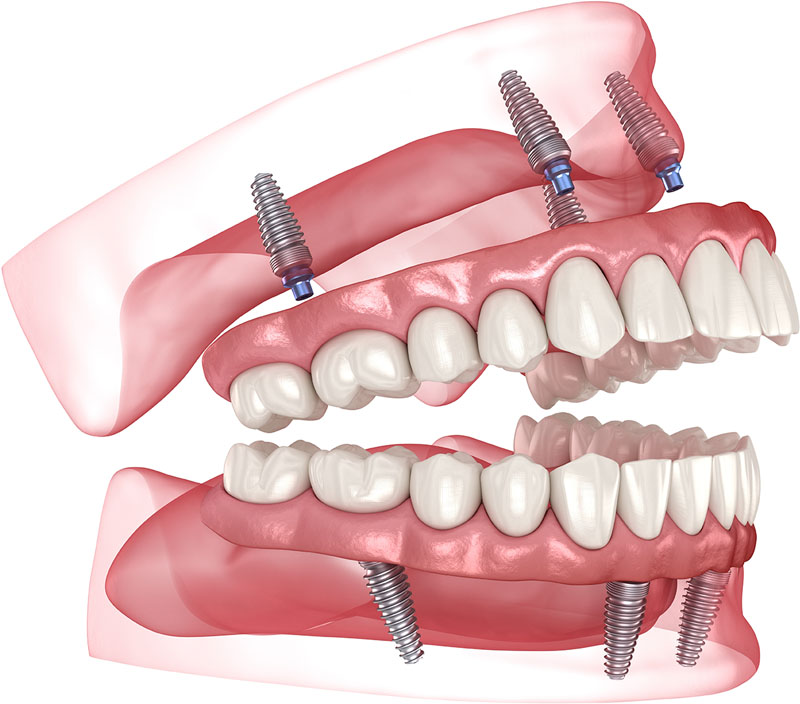

Crowns and conventional bridges or dentures may not be your only options when replacing missing teeth. Dental implants offer a smile that looks and feels very natural. Surgically placed below the gums over a series of appointments, implants fuse to the jawbone and serve as a base for individual replacement teeth, bridges or a denture.

Dental implants are the most realistic tooth replacements available. Implants begin with a surgically placed post that is securely anchored into the jawbone. The bone surrounding the anchor will heal in approximately six months. With a completely solid and stable anchor point, an artificial tooth is then installed. The end result is a new artificial tooth that is virtually indistinguishable from a natural tooth, both from an aesthetic and functional standpoint. In cases where several teeth are missing, dental implants can also act as the teeth to which bridges are fixed, again perfectly mimicking the function of healthy, natural teeth.

An implant denture may be the answer. Usually two to four implants are surgically placed in the bone and become anchored as the bone heals and secures itself to the implant. This healing process takes about six months after which the dentist can begin constructing an implant denture. An implant denture is a removable denture with attachments on the underside that clip onto a bar connected to the implants. The attachments and bar hold the denture in place and keep it from moving when chewing and speaking. Implant dentures can be classified into two groups: Implant Retained Dentures and Implant Supported Dentures. Implant Retained Dentures are held in place by the attachments, but are mainly supported by the bone and gum tissue as is a conventional denture. Implant Supported Dentures are for patients who do not have sufficient bone and supporting gum tissue. This denture is mainly supported by the bar attached to the implants.